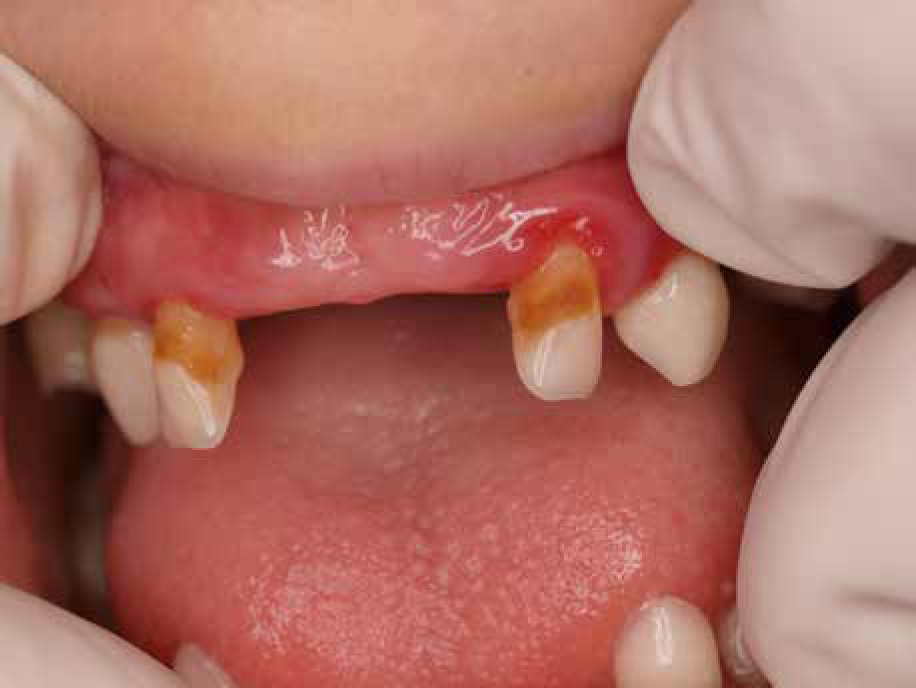

When the patient was 10, the exposure of two-thirds of palatal roots and third-degree loosening of teeth were observed (Fig. 3). A panoramic radiograph picture was taken (Fig. 4), which revealed complete absence of the bone base in all permanent first molars. Teeth 16 and 26 were qualified for extraction, which was performed in an outpatient setting under local anesthesia and antibiotic treatment (clindamycin, 10 mg/kg/dose). The obtained material from granulomatous lesions was submitted for histopathological examination, the results of which indicated non-specific inflammatory granulation tissue.